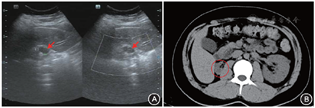

先证者,男,23岁,未婚,因“发现蛋白尿2年余”入院,院外一直未治疗。入院前半个月发现血糖升高,无明显口干、多饮、多尿,无多食及消瘦,否认高血压病史。体格检查:身高178.0 cm,体重73.5 kg,体质指数23.2 kg/m2。生长发育正常,体型适中,心肺听诊未闻及异常,腹软,全腹无压痛,肝脾肋下未触及,双肾区叩痛阴性,双下肢无浮肿,四肢活动正常,病理征阴性。父母均体健,否认近亲婚配,否认家族性遗传疾病史,空腹血糖均在正常范围内。实验室检查:入院时随机静脉血糖7.11 mmol/L,糖化血红蛋白8.4%(正常参考值范围4.0%~6.0%)。馒头餐试验:空腹、60 min、120 min血糖:5.79、12.52、13.92 mmol/L,空腹、60 min、120 min胰岛素:47.24、146.40、283.93 pmol/L,空腹、60 min、120 min C肽:0.45、0.85、2.11 nmol/L。血肌酐143 μmol/L(40~120 μmol/L),尿酸530 μmol/L(178.4~493.7 μmol/L),胱抑素C 1.57 mg/L(0.59~1.03 mg/L),尿常规尿蛋白弱阳性,尿微量白蛋白187 mg/L(0~30 mg/L),尿免疫球蛋白G 20.8 mg/L(0.00~8.50 mg/L),尿转铁蛋白7.94 mg/L(0.00~2.20 mg/L),尿α1-微球蛋白13.4 mg/L(0.00~12.20 mg/L),尿β2-微球蛋白0.41 mg/L(0.00~0.22 mg/L),24 h尿蛋白定量481 mg/24 h(24~141 mg/24 h),血清镁离子0.50 mmol/L(0.75~1.05 mmol/L)。血清游离三碘甲状腺原氨酸及游离甲状腺素正常,促甲状腺激素5.020 mIU/L(0.350~4.940 mIU/L),甲状腺相关抗体检查阴性,抗核抗体全套中抗组蛋白抗体临界阳性、余均为阴性,血管炎抗体全套阴性。影像学检查:肝胆胰脾腹腔B超未见异常,泌尿系彩色超声:右肾萎缩伴多发囊性结节,左肾弥漫性病变伴多发囊性结节(图1A)。泌尿系及胰腺CT平扫右肾重度萎缩,双肾囊肿,胰腺未见囊肿(图1B)。眼科检查:双眼眼底视盘界清,视网膜面未见明显出血渗出。